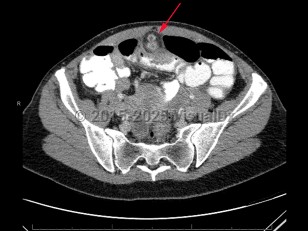

A Meckel diverticulum is a remnant of the omphalomesenteric duct in the distal ileum. Patients with a Meckel diverticulum typically present with painless hematochezia and/or bowel obstruction. Alternatively, a Meckel diverticulum should be considered if an abdominal mass is detected or in cases of abdominal pain, often right lower quadrant, of unclear etiology.

A Meckel diverticulum can predispose patients to intussusception, ulcer formation, bowel inflammation, perforation, or foreign body entrapment, all occurring at the diverticulum.